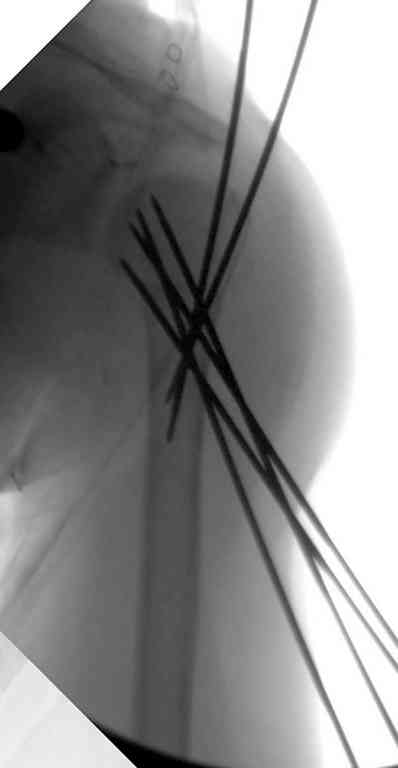

Неправильно выбранная тактика по фиксации или технические ошибки во время операции могут привести к серьезным осложнениям. Здесь привожу

пример из нашей практики, вроде обычный перелом шейки, фиксированный популярным методом "Сиэтла" - множественными спицами 2.8 мм с резьбой на конце.

При первичном осмотре в поликлинике через 3 недели обнаружили миграцию двух спиц, срочно госпитализированному на второй день перед операцией на всякий случай сделали снимок, одна спица находилась под ключицей в шейном отделе (на снимке).